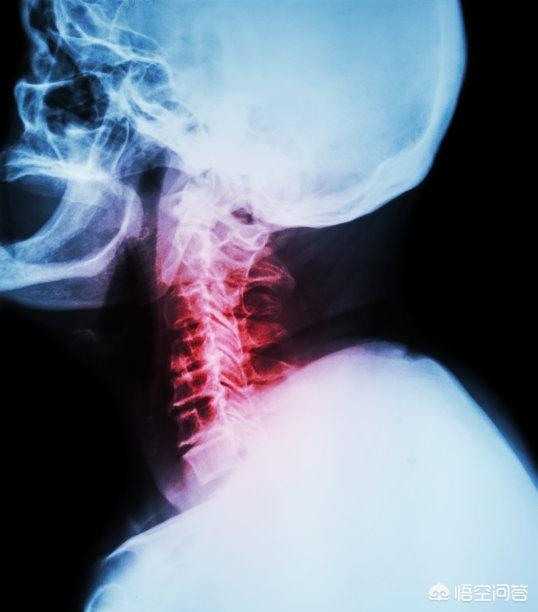

L'incidence de la spondylose cervicale est de plus en plus élevée et l'âge d'apparition est de plus en plus jeune. La spondylose cervicale est une maladie basée sur des changements pathologiques dégénératifs. La spondylose cervicale est une maladie basée sur des changements pathologiques dégénératifs. Il s'agit d'un syndrome clinique d'une série de dysfonctionnements qui se produisent principalement en raison d'une déformation prolongée de la colonne cervicale, d'une ostéomalacie ou d'un prolapsus des disques intervertébraux et d'un épaississement des ligaments, qui entraînent la compression de la moelle épinière cervicale, des racines nerveuses ou de l'artère vertébrale.

La spondylose cervicale est un processus pathologique dégénératif progressif impliquant les corps vertébraux et les disques intervertébraux de la colonne cervicale. Il en résulte un rétrécissement du canal rachidien au centre de la colonne cervicale (sténose), une compression de la moelle épinière cervicale et l'apparition d'un syndrome de dysfonctionnement de la moelle épinière (spondylose cervicale spondylotique). La spondylose spondylotique survient chez 5 à 10 % des patients présentant une spondylose cervicale symptomatique. D'autres syndromes cliniques associés à la spondylose cervicale comprennent la cervicalgie et la radiculopathie cervicale.